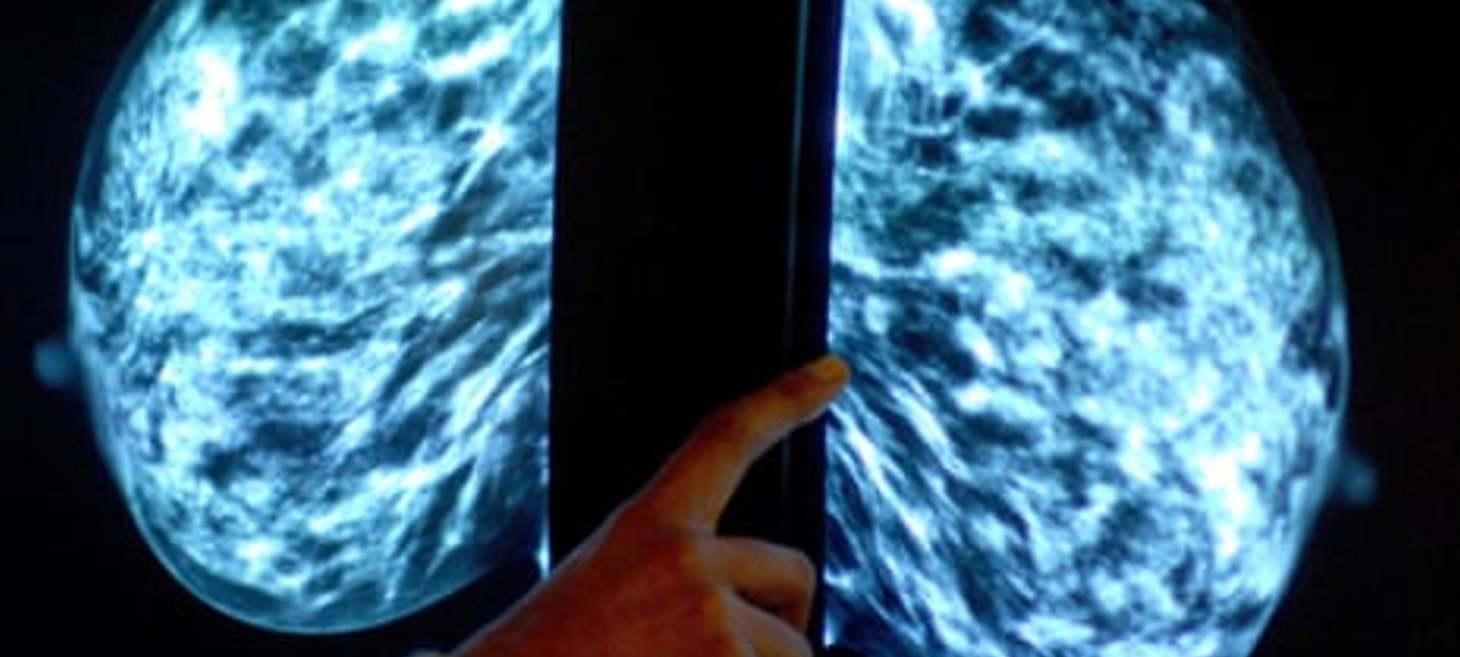

NHS to launch world’s biggest trial of AI breast cancer diagnosis

If successful, the scheme could speed up testing and reduce radiologists’ workload by around half The NHS is launching the world’s biggest trial of artificial intelligence to detect breast cancer, which could lead to faster diagnosis of the disease. AI will be deployed to analyse two-thirds of at least 700,000 mammograms done in England over the next few years to see if it is as accurate and reliable at reading scans as a radiologist.